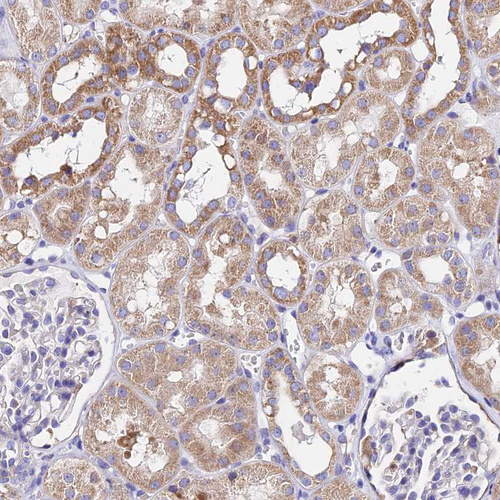

Immunohistochemical staining of human fallopian tube shows moderate cytoplasmic positivity in glandular cells.